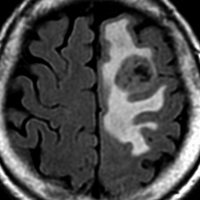

テント上 退形成性上衣腫 グレード3:EPN-ST-RELA negative

膠芽腫を思わせるような,腫瘍内部の壊死,のう胞形成,出血があります。高度の血管増生と動静脈シャントがあり,早期腫瘍静脈描出 early venous fillingがみられます。10代のおそらく右側脳室三角部辺りから発生した退形成性上衣腫です。激しい出血がありましたが全摘出 gross total removal しました。リスクをかえりみない手術も必要です。画像所見も病理組織像も超悪性腫瘍なのですが,治る可能性があるタイプです。

テント上 上衣腫 グレード2

成人に発生したものです。境界が明瞭な腫瘍で,周囲にとても強い脳浮腫があります。